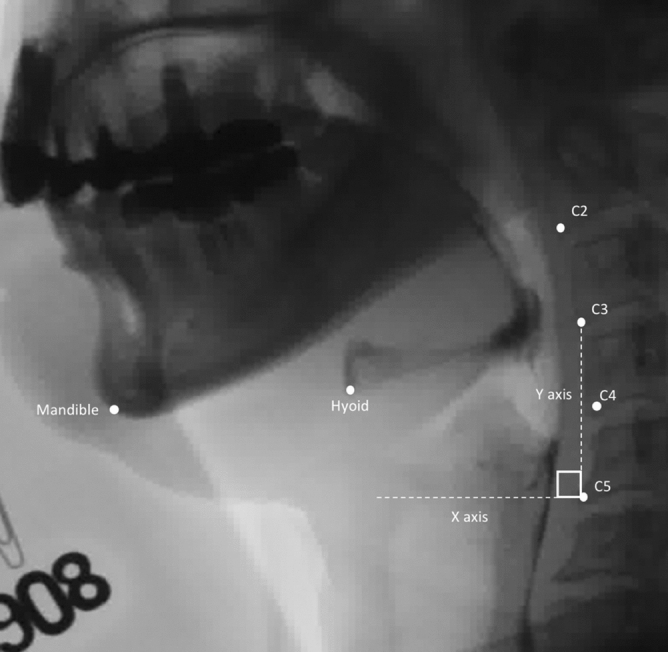

For labeling the points of interest on VFSS image, engineers of AetherAI Co., Ltd. constructed a web-based labeling interface software with the front-end framework built up with the Angular platform (Ver. 10.1.4) and the backend framework built up with Django framework (Ver. 2.2.10). With this web-based labeling software, users could not only mark the points of interest but also adjust the contrast of each image frame in order to improve the accuracy during image labeling. Two trained physiatrists (K.-C.W. and S.-H.C.) and two speech and language pathologists (Y.-C.W. and Y.-Y.P.) marked the following points of interest in each video frame using the AetherAI platform (Fig. 1): (1) anterior–inferior corner of the C2 vertebral body, (2) anterior–inferior corner of the C3 vertebral body, (3) anterior–inferior corner of the C4 vertebral body, (4) anterior–inferior corner of the C5 vertebral body, (5) anterior–inferior corner of the hyoid bone, and (6) the most prominent point at anterior–inferior corner of the mandible bone. To further conduct the hyoid kinematic analysis, a coordinate axis was defined with the anterior–inferior corner of the C4 vertebral body set as the origin. The y-axis was defined as the line connecting (2) and (4). The perpendicular line intersecting with (3) was defined as the x-axis. Based on the established coordinate axis, the anterior-inferior corner of the hyoid bone then possessed a position coordinate and parameters including the maximal displacement of hyoid bone during swallowing, the maximal displacement in the x-axis direction, and the maximal displacement in the y-axis direction were recorded. The maximal displacement of hyoid bone was the hypotenuse displacement from the origin calculated with Pythagorean theorem. The distance was measured by transforming the image pixels to corresponding millimeters (mm) and time duration between start and end points of hyoid movement in one swallow was recorded. The starting point was defined as recognizable initiation of hyoid motion while the end point was defined as termination of hyoid motion after swallowing. The average velocity of the hyoid bone movement including the x-vector and y-vector components were also calculated by dividing the hyoid bone displacement by the duration of hyoid movement.

Figure 1.

Points of interest and coordinate axis of VFSS image with Y-axis defined as the line connecting anterior–inferior corner of C3 and C5 vertebral bodies.